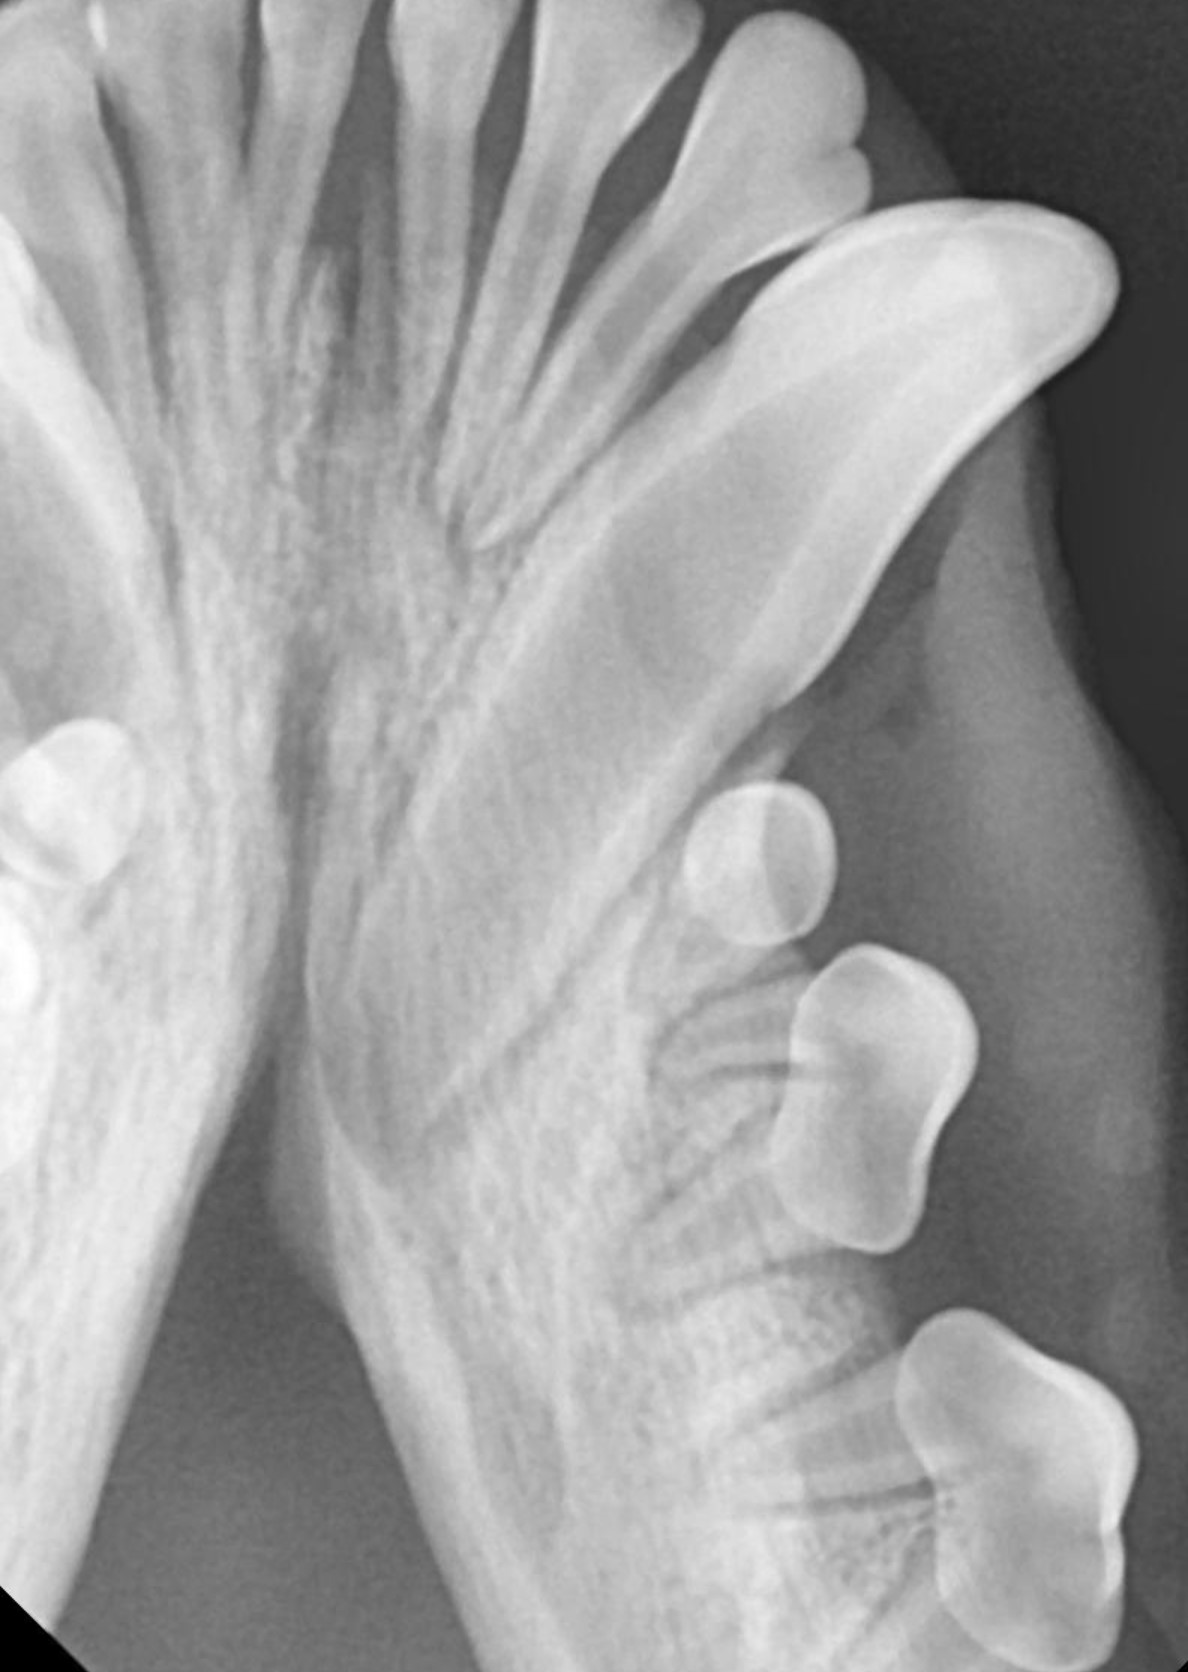

치과 X-ray 검사를 통해 정확한 진단을 한 후

다음은 에나멜 결손으로 내원한 아이의 치료 사례입니다.

강아지 법랑질 결손 송곳니가 깨진 것 같다고 내원하셨습니다.

사진을 보면 차아 표면이 울퉁불퉁하고 거칠며 아래쪽은 깨져나간 것처럼 보입니다.

방사선 검사상 첨부(설명?? 뭔지)가 아직 열려있고 다른 이상은 발견되지 않습니다.

에나멜이 결손 된 부위에 신경 노출이 확인되지 않고, 첨부가 열려 있기 때문에 손상을 방지하기 위한

보존 치료를 진행하였습니다.